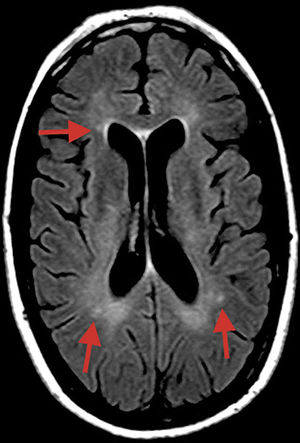

La RM nos puede ayudar al diagnóstico precoz en ciertos casos gracias a la visualización de microinfartos en la porción central del CC en cortes sagitales FLAIR y T2, las lesiones asemejan «copos de nieve» que posteriormente evolucionan a agujeros negros y atrofia centro-callosos. Estas lesiones presentan un tamaño de 3-7mm, y sugieren oclusión de precapilares de pequeño tamaño por debajo de 0,1mm (100μm de diámetro). Los microinfartos pueden adquirir forma de rayos. También se reconocen imágenes hiperdensas en difusión en cápsula interna que adoptan la forma de «collar de perlas». La presencia de dichas imágenes asociadas a lesiones centro-callosas es inequívocamente patognomónica de SS2. Aunque la mayor parte de los casos con SS no muestran afectación en la RM3.

En la RM al inicio del cuadro se visualizaron pequeñas lesiones hiperintensas inespecíficas en T2-FLAIR en la sustancia blanca subcortical, cuerpo calloso y pedúnculos cerebelosos (fig. 1).